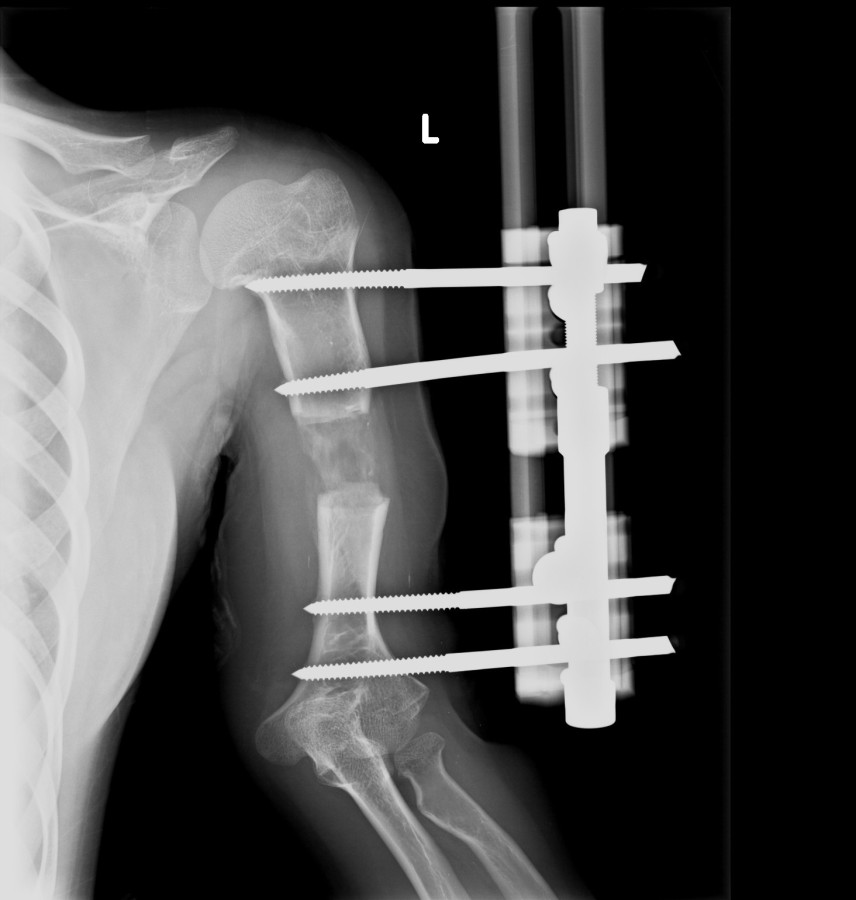

13-15 yaşlar arasında Her iki humerusu (kol) 8-12 cm boy uzatma Dirseklerin fleksiyon deformitesini düzeltme Ortalama eksternal fiksasyon tedavi süresi = 6-8 ay Alt uzuvların iki uzatması arasında üst uzuvlar uzatılarak alt uzuvların dinlenmesi sağlanmış olur. Cihaz çıkartıldıktan sonra en erken ikinci uzatmaya başlama süresi 6 aydır. Bilateral femoral uzatmalarda uzatma fazı sırasında hastanın yürümesi mümkün değildir. Ayakta durmaya sadece hasta transferi sırasında izin verilir. Uzatma fazında ambulasyona sadece tekerlekli sandalye ile izin verilir. Konsolidasyon fazında ise tedrici olarak daha fazla yük verilmesine ve cihazın çıkmasına yakın serbest yürümeye izin verilir. Bilateral tibial uzatmalarda ilk günden itibaren yürüteç veya koltuk değneği ile hastanın yük vermesine izin verilir. Uzun gezintiler tekerlekli sandalye ile yapılmalıdır. Bilateral humeral uzatmalarda hemen hemen hiçbir aktivite kısıtlaması yoktur. Uzatma süresince her iki haftada bir yapılan takiplerde kantitatif duyusal sinir testleri doktor tarafından yapılmalıdır. Bu gelişmekte olan sinir sorunlarını klinik olarak ortaya çıkmadan yakalamaya izin verir. Femoral ve humeral uzatmalarda çok nadir görülmesine rağmen tedavi edilmedikleri durumda düşük ayağa (ayağı yukarı çeken kasları innerve eden sinirin felci) neden olabilirler. Eğer erken tespit edilir ve uzatmanın hızı azaltılırsa, sinir problemi genellikle kendiliğinden düzelir ve uzatmaya düşük hızda devam edilir. Uzatmada yavaşlamaya rağmen sinir problemi devam ederse sinirin cerrahi olarak gevşetilmesi gerekir. Bu işlem 1cm’ lik bir kesi ile yapılabilen ve hastanede bir gece kalmayı gerektiren küçük bir işlemdir. Bu ameliyat el bileğinde sinir sıkışması (karpal tünel sendromu) için yapılana benzerdir.